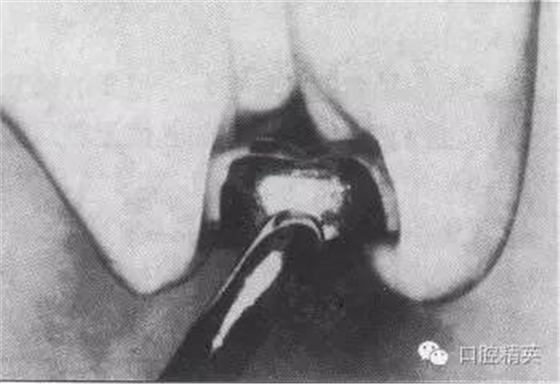

1)牙體制備:首先清潔牙面,去除齲蝕組織。鄰面的制備,經(jīng)牙體的切割使近遠(yuǎn)中面相平行,或使牙體呈很輕微的圓錐形。若第二乳磨牙為牙列中最后一個(gè)牙時(shí),遠(yuǎn)中面的制備比近中面稍深達(dá)齦下。牙頸部不能有肩臺(tái)。

頰舌面一般不需要制備,除非頰面近頸部1/3處特別隆起,此處預(yù)備時(shí)應(yīng)掌握適度,以免使牙體與預(yù)成冠間的空隙過(guò)大。頰舌面與鄰面相交線角應(yīng)制備成圓鈍移行狀。

頜面制備應(yīng)注意對(duì)頜關(guān)系,著重切割頜面嵴。在頜面一般以去除1.0mm的牙體表面為佳。

3)修整預(yù)成冠:參照所制備牙的牙冠高度及頸緣曲線形態(tài),剪除、修整預(yù)成冠的高度及頸緣,頸緣以達(dá)齦下0.5-1.0mm為妥。用各種冠鉗調(diào)整頜面的凹凸、恢復(fù)牙冠應(yīng)有的隆起、縮緊牙頸部,盡力形成合適的解剖形態(tài)。

4)磨光頸緣、試戴合適:用金屬剪修剪過(guò)的頸緣必須以細(xì)砂輪、橡皮輪等磨光,以免刺傷牙齦。粘固前必須調(diào)試,仔細(xì)檢查頜面有無(wú)過(guò)高、牙頸部是否密合、成品冠的軸對(duì)修復(fù)牙及其在牙列中是否協(xié)調(diào)并觀察其與鄰牙的關(guān)系等。